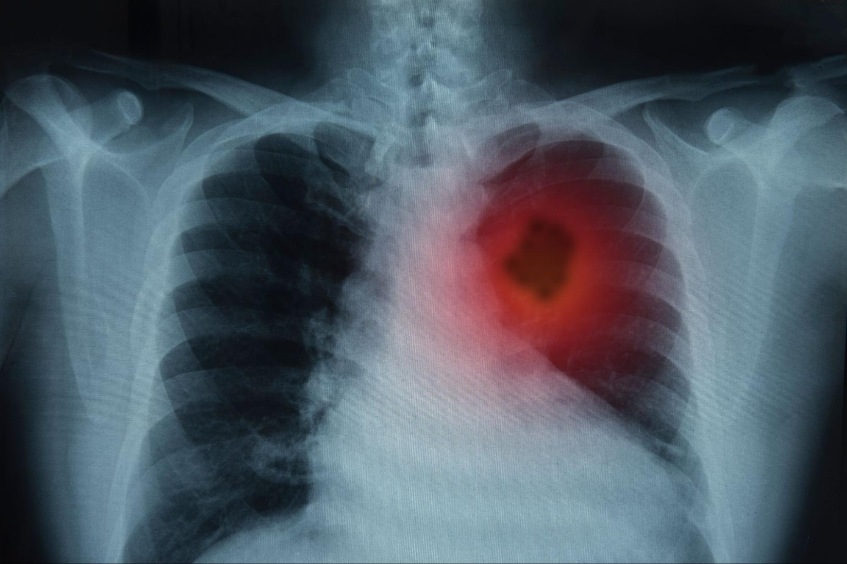

Ung thư phổi.

Ung thư phổi có thể là nguyên nhân gây tim đập nhanh và khó thở.